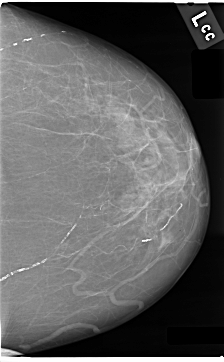

C_0031_1.LEFT_CC

LEFT_CC LINES 4696 PIXELS_PER_LINE 2904 BITS_PER_PIXEL 12 RESOLUTION 50 NON_OVERLAY